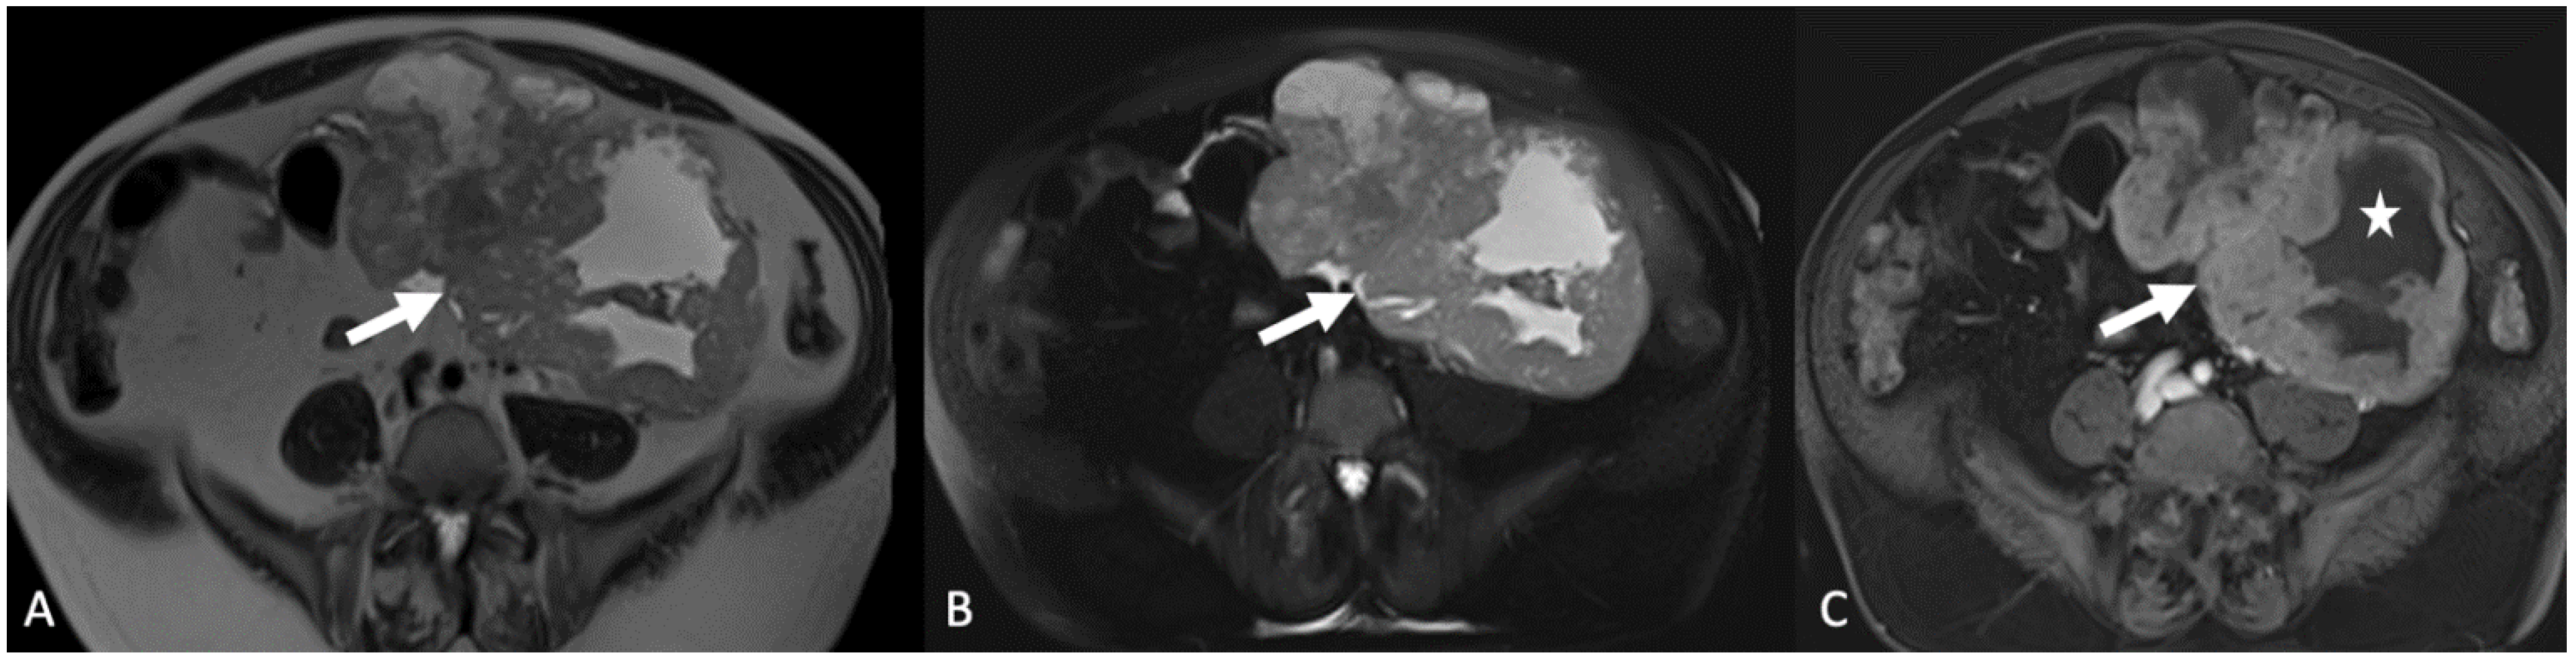

5.4. Gastrointestinal Lesions

5.4.2. Appendiceal Mucocele and Pseudomyxoma Peritonei